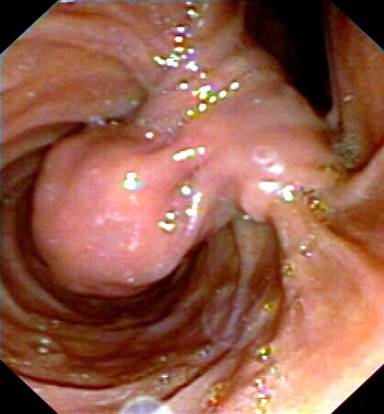

Computed tomography recognized a mass of the duodenum (Figure 1). However, magnetic resonance imaging did not reveal any lesion. Radiological differential diagnosis included gastrointestinal stromal tumor or adenoma. A magnetic resonance cholangiopancreatography was performed showing dilatation of the common bile duct (diameter equal to 9 mm) and gradually narrowing of its diameter downwards. Endoscopic retrograde cholangiopancreatography (ERCP) revealed a submucosal tumor located in the second portion of the duodenum. The lesion was seen as a large pedunculated polypoid mass originating from the second part of the duodenum in close proximity with the ampulla of Vater (Figures 2 and 3). No cholangiography was performed due to failure of cannulation of the bile duct. The pancreatic duct was normal without dilatation in its body or narrowing of its size. A sphincterotomy was performed 6 mm along the pancreatic sphincter, as it is considered an endoscopic therapy for chronic pancreatitis with papillary stenosis [8]. Two months after the procedure of sphincterotomy, the patient had another episode of acute pancreatitis without jaundice. Hence, the obstruction of the pancreatic duct due to the intermittent movements of the mass was considered as the cause of the episodes of acute pancreatitis. The patient was referred for surgical consultation and regional resection was decided. The operation was performed one month after the last episode of acute pancreatitis. Intraoperatively (Figure 4), there was no sign of lymph node metastases or local extension of the tumor.

Figure 2. Proximal view of the tumor. |